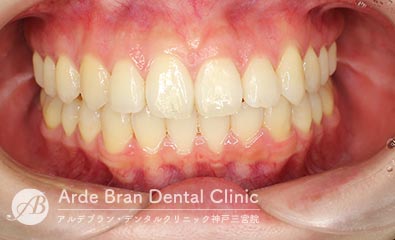

- 叢生/八重歯/歯のがたつき(20代女性 治療期間2年)

- 上下の犬歯の突出と歯のがたつきを主訴に来院されました。特に上下ともに犬歯が大きく前に出ており、噛み合わせに悪影響を及ぼしている状態でした。歯列のスペース不足が顕著であったため、上下左右の第一小臼歯を4本抜歯し、適切な歯列を確保する方針としました。治療では、上下の犬歯を正しい位置へ誘導しながら、全体の噛み合わせを調整。歯列のアーチを整え、前歯のねじれやガタつきも改善しました。治療後は、上下の犬歯が適切な位置に収まり、口元のラインがすっきりと改善。歯並びだけでなく、噛み合わせや清掃性の向上にもつながり、機能的で美しい口元を実現しました。

- 治療前

- 治療後

| 装置名 | インビザライン(マウスピース矯正) |

| 抜歯非抜歯 | 4本抜歯 |

| 治療期間 | 2年 |

| 費用 | インビザラインフル72万円+TAX |